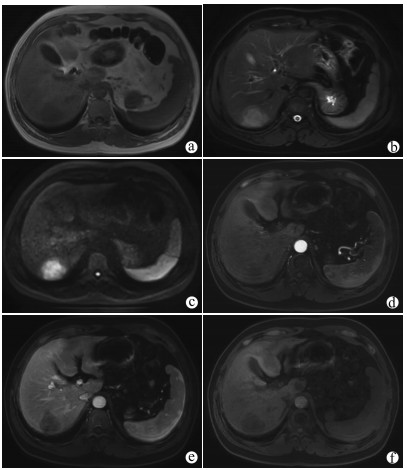

Construction of a new patient-derived xenograft model of human liver cancer in mice with normal immunity

Huixin TANG, Shanshan LI, Feng HONG, Yanzhen BI, Quanyi WANG, Xiaobei ZHANG, Shumin CHENG, Zhongping DUAN, Zhenfeng SHU, Yu CHEN

2021, 37(11): 2584-2588. DOI: 10.3969/j.issn.1001-5256.2021.11.019

Abstract(2475) HTML (633) PDF (3030KB)(178)

Abstract:

Objective  To establish a new patient-derived xenograft (PDX) model of human liver cancer by inoculating the complex of human primary liver cancer cells and a novel microcarrier (microcarrier 6) into mice with normal immune function.  Methods  Primary liver cancer cells were isolated and extracted from the fresh human liver cancer tissue of five patients and were then co-cultured with microcarrier 6 to construct a three-dimensional tumor cell culture model in vitro. According to the type of graft, 75 male C57BL/6 mice were divided into cell control group, microcarrier control group, and experimental group (each sample corresponded to three groups, with 15 groups in total and 5 mice in each group). The liver cancer cell-microcarrier complex was implanted into the mice by subcutaneous inoculation, and tumor formation time, tumor formation rate, and histopathological manifestations were observed. The Fisher's exact test was used for comparison of categorical data between two groups.  Results  As for the liver cancer cells from the five patients, tumor formation was observed in the mice corresponding to three patients. In these three experiments, tumor formation was not observed in the control groups and was only observed in the experimental groups, and 12 of the 15 mice in the experimental groups had successful tumor formation, with a tumor formation rate as high as 80%, which was significantly different from that in the cell control groups and the microcarrier control groups (all P < 0.05). The tumor formation time was 5-7 days; the xenograft tumor grew rapidly, and HE staining showed nested or flaky cells with obvious heteromorphism, with the presence of pathological mitosis; immunohistochemical staining showed positive CK8/18, Hep, and Gpc-3, which was in accordance with the characteristics of human liver cancer cells.  Conclusion  This experiment successfully establishes a new PDX model of human liver cancer based on the complex of microcarrier 6 and human primary liver cancer cells in mice with normal immunity. This model can be used to better elucidate the mechanism of the development and progression of liver cancer in the body with normal immunity, and besides, it also provides a new animal model with higher value for the precise treatment of liver cancer.